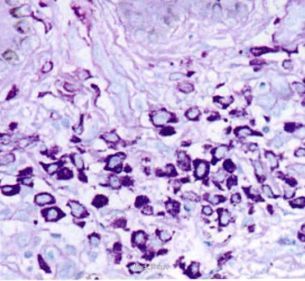

皮肤科检查:躯干、四肢泛发粟粒至黄豆大圆形或椭圆形暗红色斑丘疹.散在分布.以躯干为主.Darier征阳性。实验室及辅助检查:未见异常。皮损组织病理检查:表皮正常.真皮内可见单一核细胞弥漫浸润,细胞中等大小、形态一致,核呈圆形、卵圆形或肾形,位于细胞中央,胞质淡染或透明,核分裂象偶见;真皮浅层尚可见灶性淋巴细胞浸润:吉姆萨染色可见部分细胞内有紫红色嗜异染颗粒。

诊断:皮肤肥大细胞增生症。治疗:口服左西替利嗪5 mg Qd及复方甘草酸苷50 mg tid,治疗15 d后观察有一定疗效。